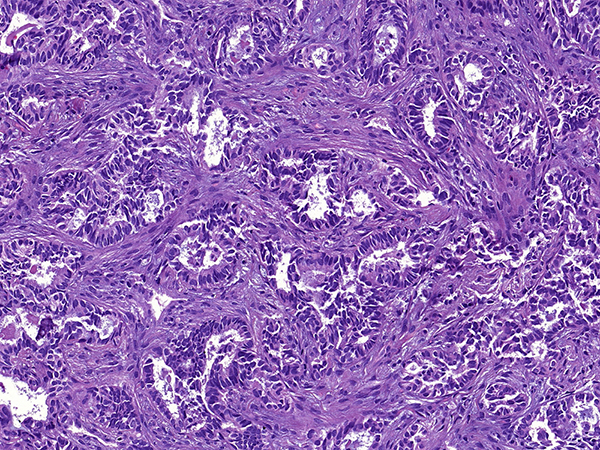

Clinical History: A 70-year-old woman consulted our hospital for a second opinion. She had a history of endometrial carcinoma treated with hysterectomy 5 years prior and was free of disease at last follow-up. She was a sporadic smoker. A chest CT revealed a 3.3-cm solitary lung mass in the left upper lobe without mediastinal lymphadenopathy. CT-guided core needle biopsy was performed (Figures 1-3). Results of immunohistochemical stains are shown in Figure 4 (PAX-8), Figure 5 (TTF-1; 8G7G3/1) and Figure 6 (GATA-3). The neoplastic cells were negative for napsin A, thyroglobulin and estrogen receptors (ER).

TTF-1 is a widely used immunohistochemical marker of lung origin. The clone 8G7G3/1 is more specific than SPT24 and SP141. However, even the 8G7G3/1 clone of TTF-1 can be positive in adenocarcinomas from primary sites other than the lung. In the differential between primary lung adenocarcinoma and metastasis to the lung from sites such as the endometrium, kidney and thyroid, it is important to remember that PAX-8 is negative in the vast majority of primary lung adenocarcinomas. In a recent study of 418 resected primary lung carcinomas, not even a single case showed strong and diffuse PAX-8 staining.

Take home message for trainees: Strong and diffuse PAX-8 staining in an adenocarcinoma strongly suggests a non-pulmonary primary.